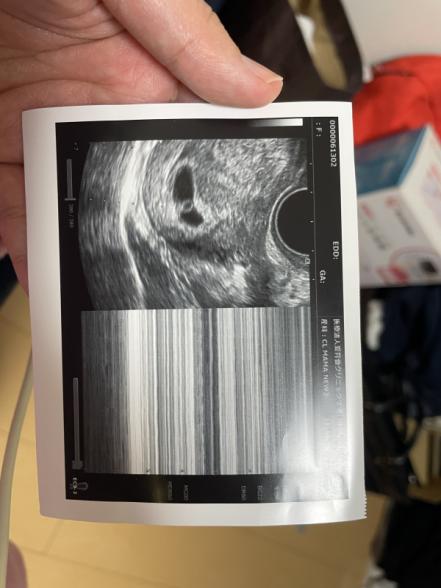

6週5日で心拍確認でした。

ただ6週5日にしては赤ちゃんのサイズが小さい。

Mモードでは確かに波打っており、

先生も、エコー写真を見せながら

これが赤ちゃん、この波が心拍と言いました。

私にはあまりにも小さく、Mモードの波もよく分かりませんでした。

エコー写真を載せますが、卵黄嚢だけ大きいような気がします。。

赤ちゃんのサイズが小さいと言われていたこともあったのですね。エコーのお写真を拝見いたしましたが、看護師さんが出来立てほやほやと言われるぐらいなので、より卵黄嚢が大きく感じられることもあるのではと思いました。

リングの先の小さな石のような感じで赤ちゃんが確認できる頃かと思います。